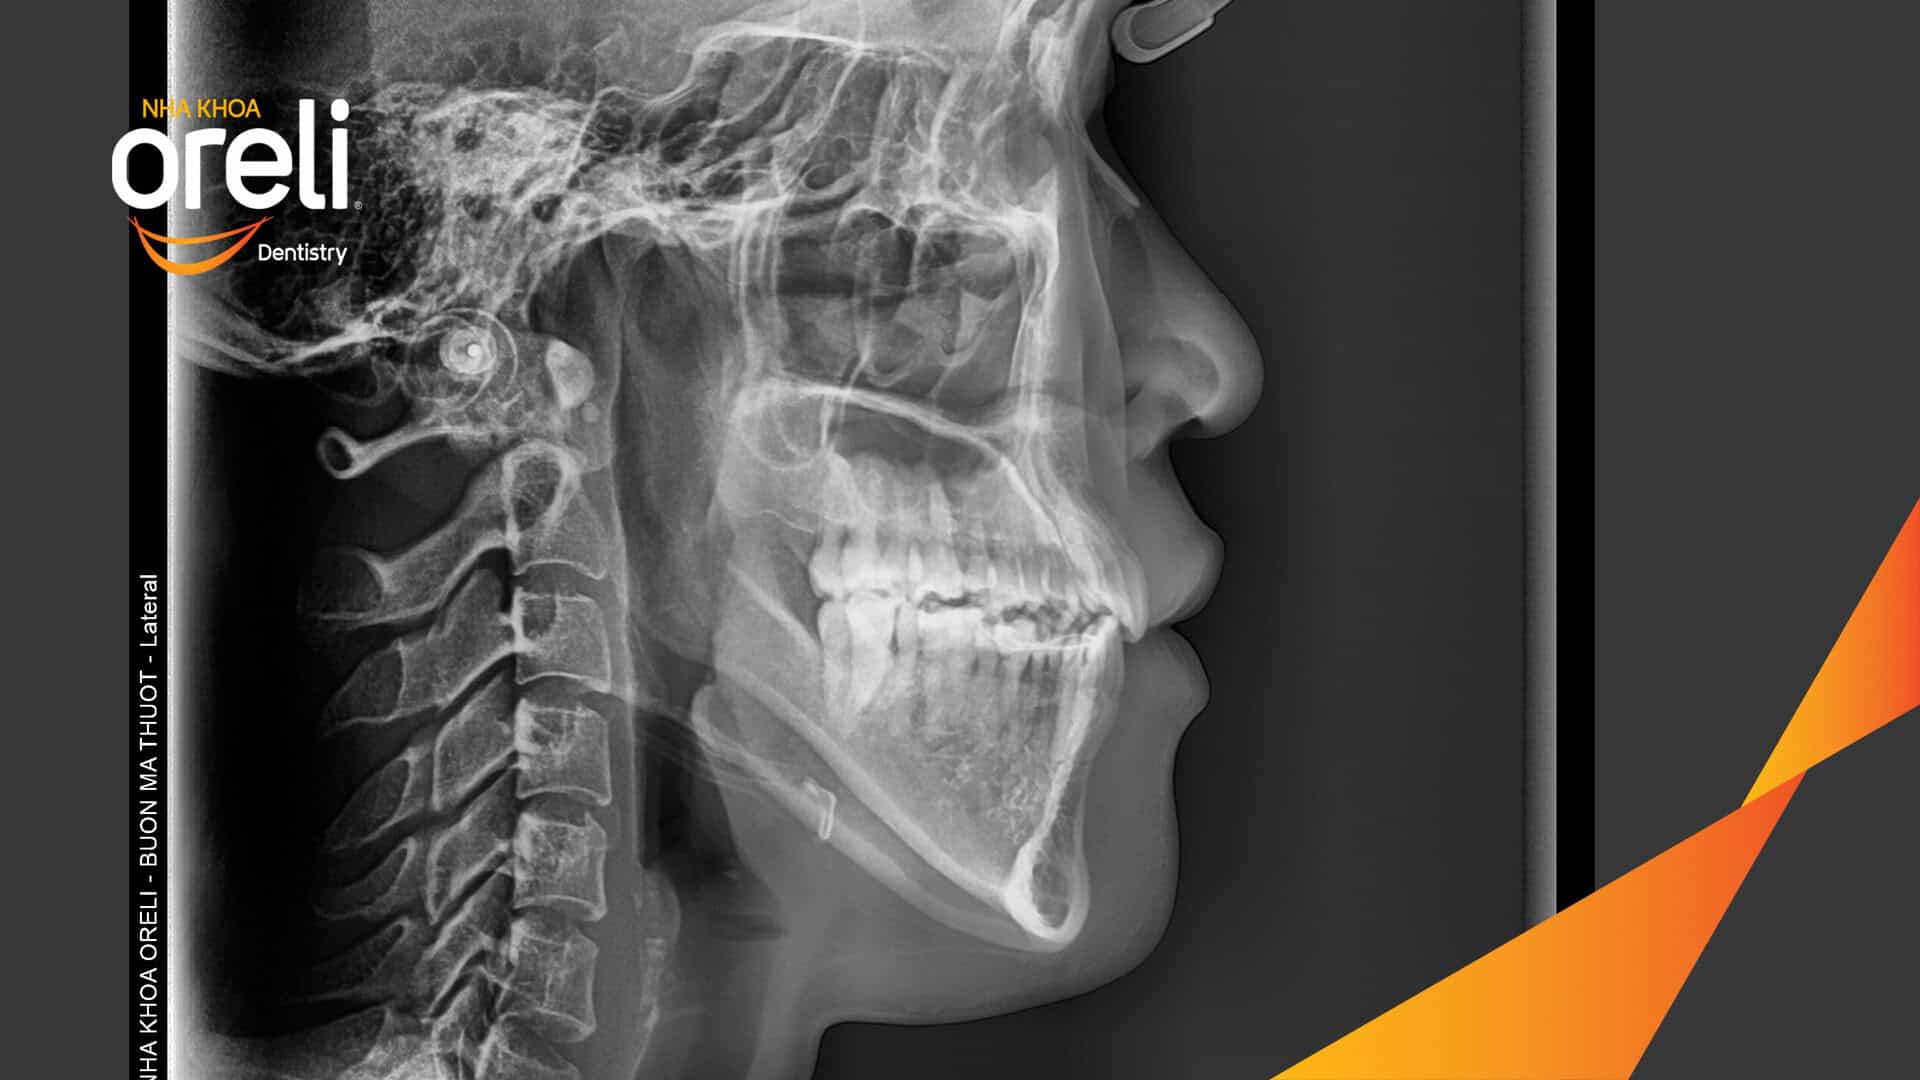

Ca niềng răng sai khớp cắn hạng 3 móm nặng có nhổ răng số 7 – Kết quả thực tế Niềng răngChỉnh lệch cằmMóm Xem thêm